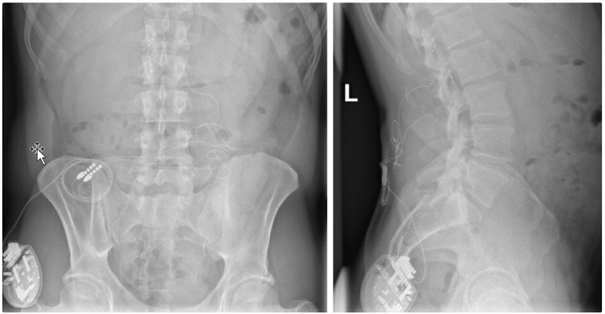

Bei Patienten mit schwerer Spastik oder chronischen Schmerzen, die nicht ausreichend auf herkömmliche medikamentöse Therapien ansprechen, kann die Implantation einer Schmerzpumpe eine effektive Lösung darstellen. Diese Pumpe ermöglicht die direkte Abgabe von Schmerzmitteln oder muskelentspannenden Medikamenten in den Nervenwasserraum (intrathekal), was eine deutlich gezieltere Wirkung mit geringeren Nebenwirkungen ermöglicht als bei in Tablettenform eingenommenen Medikamenten.

Das Pumpensystem besteht aus einem kleinen Schlauch, welcher in den Nervenwasserraum eingebracht wird und mit der Pumpe verbunden ist. Die Pumpe wird meist am Bauch unter der Haut implantiert und ermöglicht, dass die Dosierung der Medikamente exakt an die Bedürfnisse angepasst werden kann. Es ist eine regelmäßige Wiederbefüllung der Pumpe mit den Medikamenten notwendig, was ähnlich wie bei einer Blutabnahme von außen erfolgt.

In unserer Klinik bieten wir Ihnen eine ausführliche Beratung, die Implantation sowie die kontinuierliche Nachsorge dieser Therapie, um Ihre Beschwerden bestmöglich zu lindern und Ihre Lebensqualität zu steigern.

Am Bauch implantierte Medikamentenpumpe (Pfeil)